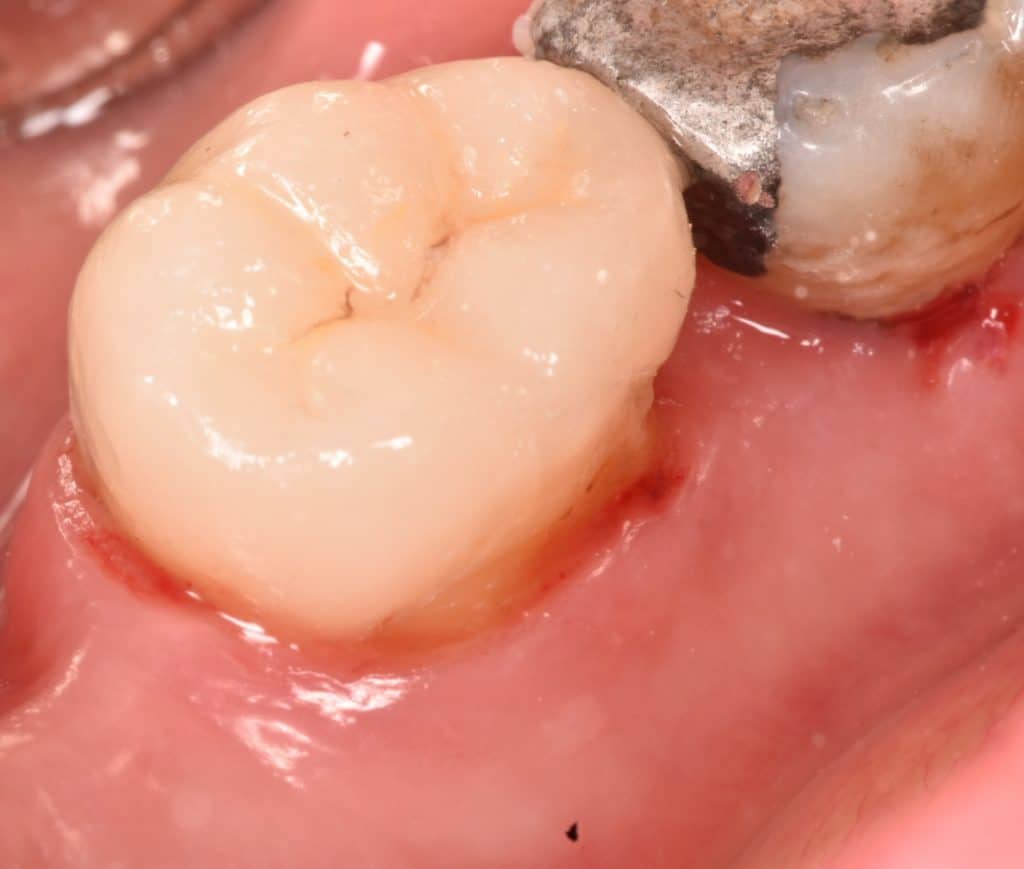

IDS with gold standard clearfil SE bond ,RC with flowable composite ,DWT ,Ever x posterior for dentin replacement ,coverd by GC composite ,biobase ready

Buccal view